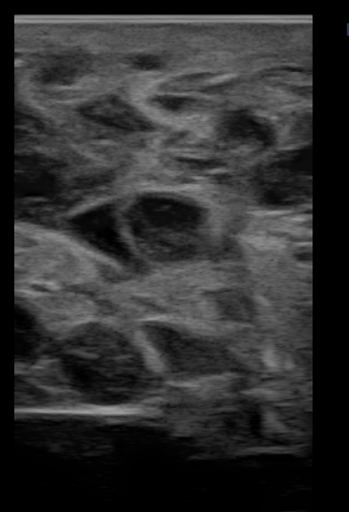

L’examen clinique général de F ne présente pas d’anomalie. Une palpation transrectale met en évidence un ovaire droit de taille augmentée. Une échographie de cet ovaire par voie trans rectale est réalisée montrant un aspect en nid d’abeille (cf photo 1). Au vu de l’aspect de l’ovaire, une tumeur de la granulosa est suspectée. Une ovariectomie unilatérale de l’ovaire droit sous anesthésie générale est proposée et acceptée par le propriétaire.

Photo 1 : Echographie de l'ovaire droit, aspect en nid d'abeille